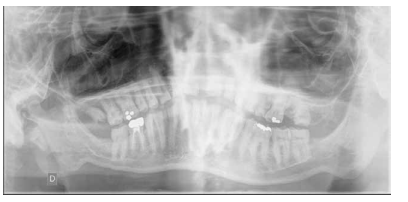

- A nivel dentario, el esmalte es uniformemente anormal, delgado, rugoso e hipoplásico. Afecta a ambas denticiones, y provocando una marcada frecuencia de fracturas dentarias, desgastes o abrasiones y caries. Existe un importante componente lingual en maloclusión, diastemas en toda la arcada y prognatismo mandibular, así como bruxismo y patología de ATM. Incisivos con forma de pala y molares cóncavos que favorece las lesiones de caries y sensibilidad dentinaria.

En la mayoría de los niños se pueden observar características dentales como cúspides puntiagudas, incisivos en forma de pala, esmalte delgado y superficies bucales con hoyos. Además, la ATM puede verse afectada con una reabsorción severa de la cabeza del cóndilo36 (Figuras 9-11).

Conviene enfatizar además la importancia de una vigilancia cercana al desarrollo dental y al cuidado bucal de manera regular para prevenir el desgaste de los dientes, la pérdida de la altura vertical de la superficie oclusal y el riesgo subsecuente de disfunción de la articulación temporomandibular (ATM).